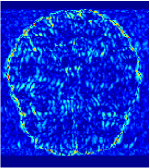

In general supervised learning, training data need to be in the same or similar distribution, heterogeneous data exhibits different structure variations of features which hinders CNNs to extract features efficiently. In our experiments, raw measurements sampled from different ratios of compressed sensing display different levels of incompleteness, these undersampled measurements do not fall in the same distribution but they are related. Different sampling masks are shown at the bottom of Figure 1 and 2 may have complemented sampled points, in the sense that some of the points which sampling ratio mask does not sample have been captured by other masks. In our experiment, different sampling masks provide their own information from their sampled points so that four reconstruction tasks help each other to achieve an efficient performance. Therefore, it explains the reason that Meta-learning is still superior to conventional learning when the sampling ratio is large.

Qualitative comparison between conventional and Meta-learning methods are shown in Figure 1 and 3, which display the reconstructed MR images of the same slice for T1 and T2 respectively, we label the zoomed-in details of HGG in the red boxes. We observe the evidence that conventional learning is more blurry and lost sharp edges, especially in lower CS ratios. From the point-wise error map, we find meta-learning has the ability to reduce noises especially in some detailed and complicated regions comparing to conventional learning.